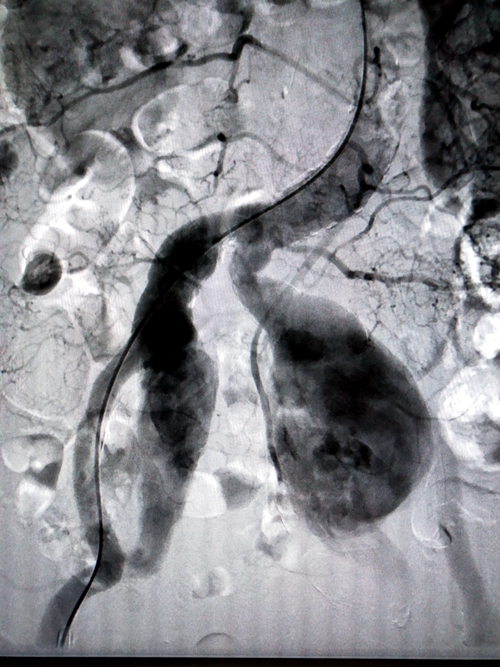

术前髂内动脉造影

收治才奶奶入院后,通过CT血管三维重建(CTA)检查明确了诊断——双侧髂总动脉瘤化并双侧髂内动脉巨大动脉瘤。考虑到才奶奶因有高血压病史,这就意味着髂内动脉瘤这两颗“定时炸弹”随时有破裂出血危及生命的可能。经医院专家会诊后决定动脉支架手术是最佳治疗方式。

手术在介入手术室进行,由胡康新教授指导,汤金城医生主刀,在DSA引导下,局麻切开右侧股动脉,在超硬导丝引导下置入一体式腹主动脉覆膜支架于腹主动脉末端及双侧髂总动脉内,并在腹主动脉一体式支架远端左右各植入一个覆膜支架,覆盖髂内动脉瘤开口,支架植入后再造影,髂内动脉瘤腔内只少量显影,随着时间的推移双侧髂内动脉瘤开口最终会完全覆盖。手术采取局部麻醉,全程患者并未有痛苦感。经过两个小时的手术,介入医生成功拆除了这两颗“定时炸弹”。

支架植入后髂内动脉造影